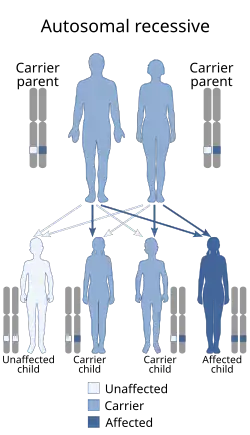

| Autosomal recessive is generally the manner in which CMD is inherited | |

Congenital muscular dystrophies are autosomal recessively-inherited muscle diseases. They are a group of heterogeneous disorders characterized by muscle weakness which is present at birth and the different changes on muscle biopsy that ranges from myopathic to overtly dystrophic due to the age at which the biopsy takes place.[1][4]

Congenital muscular dystrophies (CMDs) are autosomal recessively inherited, except in some cases of de novo gene mutation and Ullrich congenital muscular dystrophy.[8][9] This means that in most cases, both parents must be carriers of a CMD gene in order for it to be inherited. CMDs are heterogenous and thus far there have been 35 genes discovered to be involved with different forms of CMD resulting from these mutations.[10][11][12][13][8] There are different forms of CMD, often categorized by the protein changes caused by an atypical gene.

One finds that congenital muscular dystrophies can be either autosomal dominant or autosomal recessive in terms of the inheritance pattern, though the latter is much more common[1]